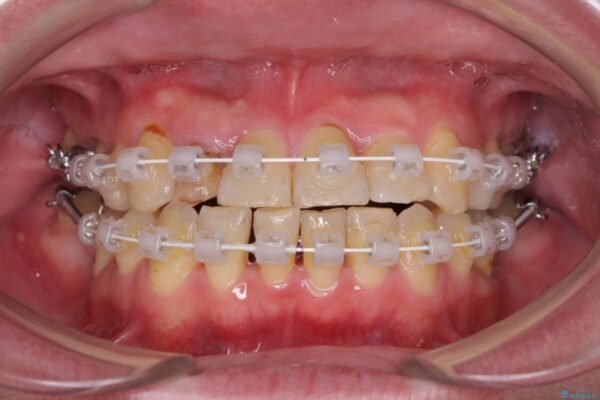

矯正治療でインプラント埋入を行い、矯正治療後に気になる前歯と合わせてオールセラミッククラウンによる補綴治療を行うこととしました。

治療途中

• 割れてしまった奥歯とデコボコの前歯 矯正治療とインプラント治療 治療途中画像